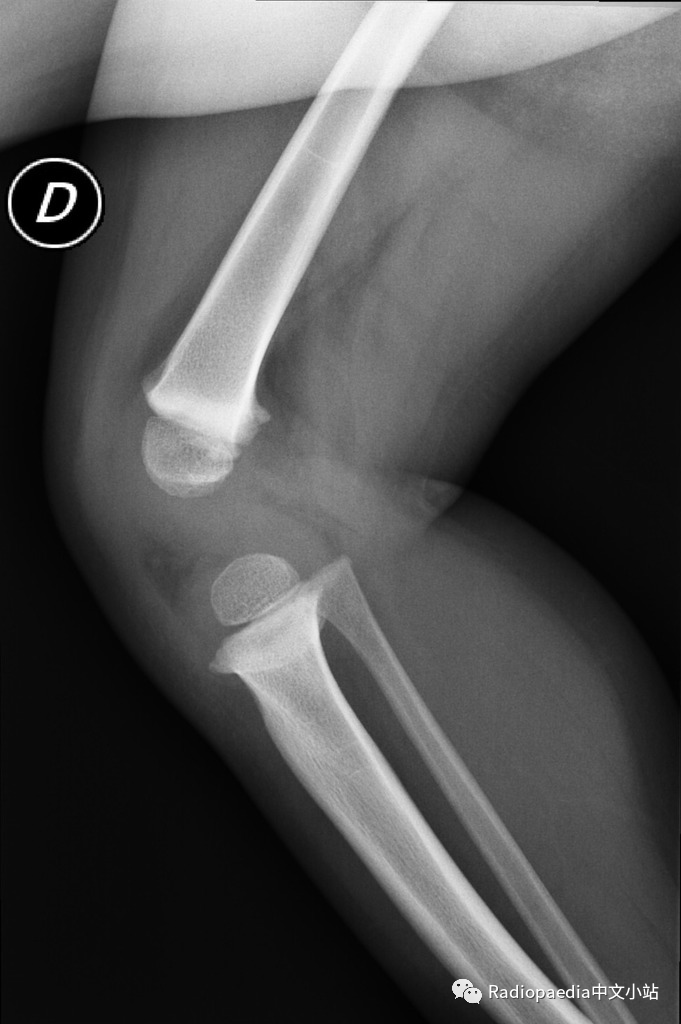

胫骨干骺端-骨干角

胫骨干骺端-骨干角:通过胫骨近侧干端的最宽处画条直线(连接内侧和外侧尖状突起处),该线与胫骨长轴的垂直线形成的角度,用于诊断Blount病。胫骨生理性弯曲(2岁以下常见)时,这个角度大约为5°,当大于11°提示 Blount病,大于20°可确诊。但是,一些研究已经开始质疑干骺端-骨干角的有效性,因为该角度的测量可能受到胫骨旋转的影响。

大部分2岁以下的婴幼儿下肢弯曲都是正常的,属于生理性改变,不需要治疗就可以消失。生理性弯曲的特点:①胫骨和股骨均向外侧弯曲;②股骨远端和胫骨近端干骺端边缘轻度致密、呈鸟嘴样突出;③胫骨和股骨的内侧骨皮质增厚;④股骨远端和胫骨近端骨内侧骨化不良呈楔形;③胫骨远侧生长板可以倾斜。

当临床出现进展性内翻,同时平片中胫骨近端出现特征性改变(干骺端内侧增宽、规则,骨皮质增厚且呈垂直走形呈鸟嘴样;内侧骨骺高度减小)时可以明确诊断。